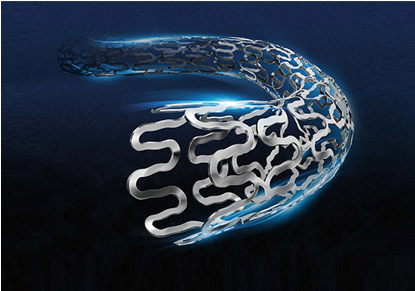

Product Description Yinyi Coronary Artery Metal Stent has an excellent...